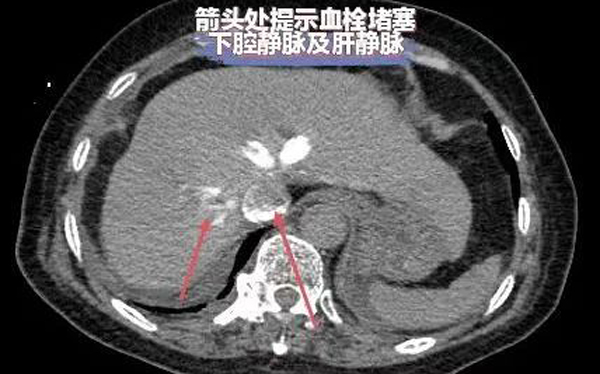

据了解,邓某,因“反复呼吸困难10余天”于外院治疗,效果不佳,症状逐渐加重,辗转多家医院来到我院,入院后患者生命体征不稳定,血压在70/40mmHg左右,心率120次/分左右,面罩吸氧状态下氧饱和度82%,D二聚体明显升高,高度怀疑肺栓塞,行急诊肺动脉CTA检查提示:右肺动脉主干及右肺下叶肺动脉分支血栓形成及下腔静脉大量血栓。